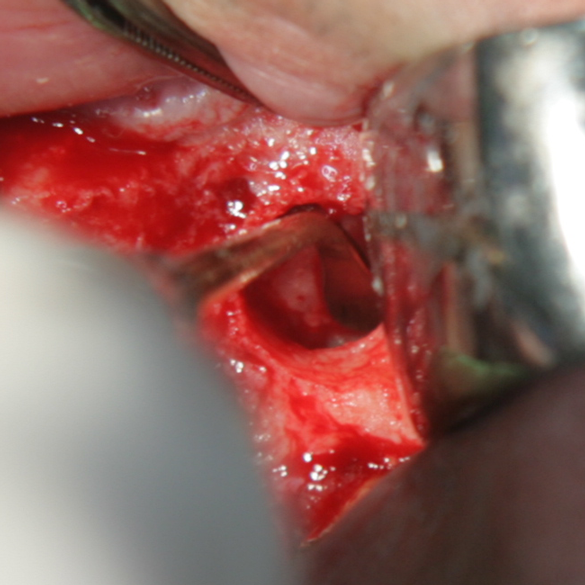

Отворен максиларен синус в началото на интервенцията. Случаят е интересен със следното - твърде атипична форма на трепанационния отвор. На какво се дължи на това - на лошо планиране на оперативния достъп или на нещо друго? Дължи се на факта, че отначало въпросната намеса беше планирана като балонен синуслифт; за съжаление обаче мембраната на синуса се разкъса и надуването на балона стана невъзможно.